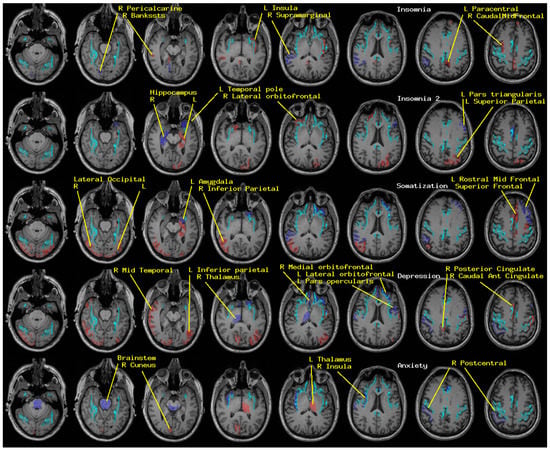

2.1. Insomnia and Psychological Distress

MEG-derived neuroelectric measures were obtained from 63 TEAM-TBI subjects at baseline and from the 40 who returned for follow-up. Symptom surveys for insomnia and three symptoms of psychological distress were obtained from all but one of the baseline subjects. Standard inventories were for insomnia (Insomnia Severity Index, ISI, [12,13]) and somatization, depression and anxiety (Brief Symptom Inventory, BSI, [14,15]). Cut-offs of 15 (ISI) and 63 (BSI) were used to divide both the baseline and follow-up TEAM-TBI recordings into clinically negative or positive groups.

Regional measures of neuroelectric activity for 17 subcortical and 68 cortical regions were combined into classifiers using stepwise linear classification [16,17,18]. Classification accuracies with p-values are shown in Table 1 (Figure 1). The p-values were computed as follows. Considering line 1 of said table, 42 of 54 TEAM-TBI subjects who screened negative for insomnia were classified as negative and 12 as positive. The chance that this would happen by chance is equivalent to the odds of getting at least 42 heads when we flip a fair coin 54 times. For each symptom, both sides of the classification have significant p-values—i.e., the classifier does well in classifying both those who screen positive and those who screen negative. This provides confidence that the neuroelectric measures which comprise the classifier are related to the symptoms.

The regions whose measures were included are shown in Table 2 (Figure 1). For each symptom, a second classification function was constructed, for which the regions that were included in the first run were excluded. This second run produced significant classification accuracy for insomnia only, as indicated in the tables. This suggests (a) elevated confidence in the relationship between the regions whose neuroelectric measures were used for each classification and (b) that the regional measures included in the second classification function for insomnia are highly correlated with linear combinations of the first set. That is why they were not included in the first classification run.

Classification accuracy reached significance for all four symptoms for both clinically negative and positive groups. These results were weakest for anxiety. Classification accuracy was comparable for baseline and follow-up records; baseline vs. follow-up clinical rating changed for insomnia (n = 10), somatization (n = 9), depression (n = 10), and anxiety (n = 15), almost all for the better.

The magnitude of the difference between the nonclinical and clinical groups was examined by testing the difference in the mean scores on each classifier between the groups. This approach provides a complementary view on the magnitude and significance of the differences between the groups achievable via measures of regional neuroelectric activity. The results are shown in Table 3. As might be expected, this produced comparable results to those shown in Table 1, albeit with greater significance.

Finally, to provide information regarding the independence of the results for the different symptoms, coincidence rates for pairs of symptoms and correlations between classifier scores are shown in Table 4. These are the same classifiers reported in Table 1 and the same classifier scores reported in Table 3. In Table 4, the left panel shows that 60% or more of the TEAM-TBI subjects have at least two of the four symptoms. Note that the acceptance criteria for the TEAM-TBI study included “high symptom burden”. The correlations (right panel) are relatively high between pairs of BSI classifier scores and relatively low between the insomnia classifier score and each of the BSI classifiers.